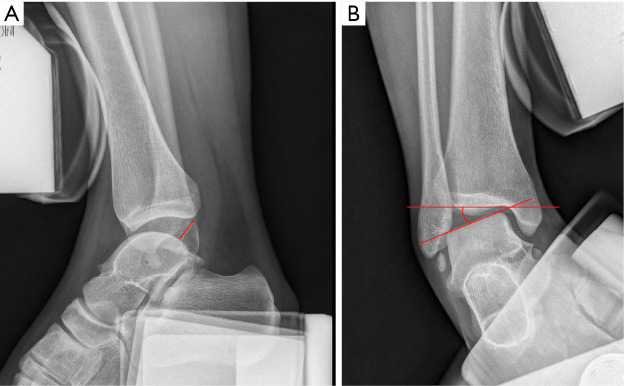

Key content and findings: In the manual examination for the diagnosis of CLAI, the anterior drawer test is the standard evaluation for lateral ligament insufficiency. The anterolateral drawer test, meanwhile, which focuses more on lateral instability biomechanically, has also been performed. Ultrasonography is a point-of-care tool that is less invasive than stress radiography and can dynamically assess ligament integrity, making the diagnosis of CLAI more accurate and convenient. Magnetic resonance imaging (MRI) is a useful modality that allows extensive preoperative evaluation of ligamentous properties and associated osteochondral damage, and it is essential in the preoperative diagnosis of CLAI.